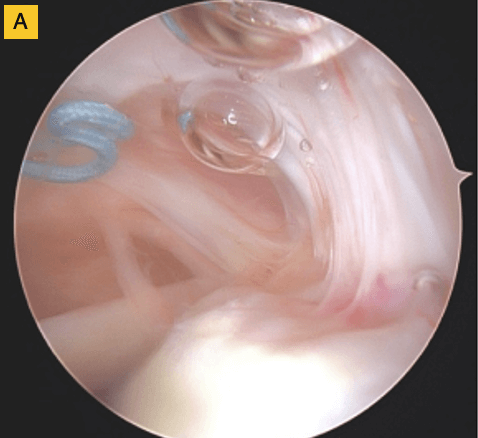

Down the road, this patient was having some bicipital pain, so we took the opportunity to look at the repair visually and performed a biceps tenodesis. You can see in this image, there's cabling of the fibers coming down onto the footprint and you can no longer see the scaffold… it’s been completely incorporated into the repair. For this patient, that was a pretty remarkable event.

(A) Tendon fibers can be seen inserting on to footprint in an organized fashion. Visible, prominent suture easily removed.

(B) BioBrace® well-synovialized and completely incorporated into the rotator cuff with new native tissue in and around the implant.